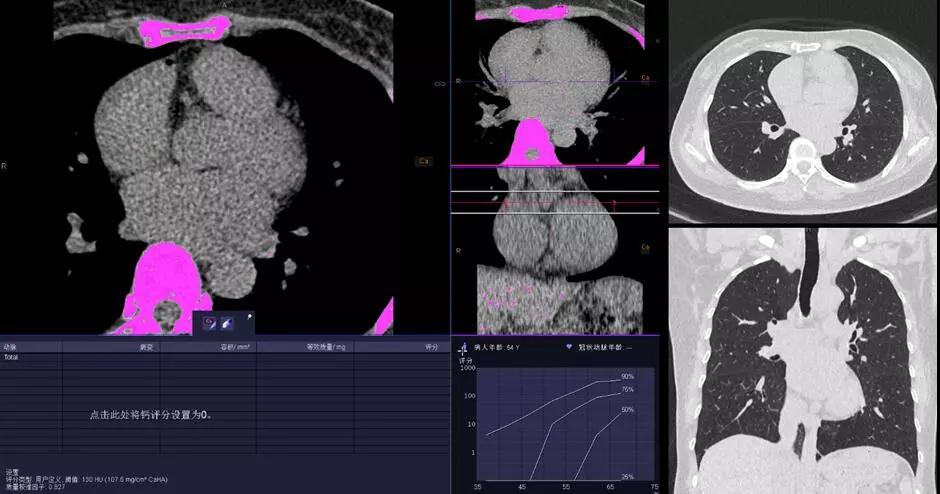

2.冠心病和腫瘤早期檢測,胸片劑量的CT掃描,徹底實現(xiàn)心肺疾病CT篩檢的常規(guī)臨床化。只需要一次胸片檢查的輻射劑量,即可完成高分辨率的肺部成像和冠脈成像;在極低的輻射劑量下同時可以保持優(yōu)秀的對比信噪比(CNR),與傳統(tǒng) CT 相比輻射劑量減少達(dá)90%。配合Stellar Infinity 全息光子探測器優(yōu)異的低對比探測能力,使 SOMATOM Force成為隱匿性病變早期檢測的理想設(shè)備。為無癥狀高?;颊叩臋z查設(shè)定了一個新的檢查標(biāo)準(zhǔn)。這無疑將改寫CT掃描的歷史。

△KV純譜技術(shù)高端體檢一站式體檢——鈣化積分+肺一站式檢查

能譜純化SPS II技術(shù)為西門子獨創(chuàng)的低劑量成像技術(shù),可提供Sn100kV、Sn150KV電壓;Sn150KV用于雙能量成像,可大幅降低雙能量成像輻射劑量常規(guī)開展;Sn100用于肺篩查,可做到0.06mSv,不到一張胸片劑量,同時肺結(jié)節(jié)檢測敏感度達(dá)到94%。